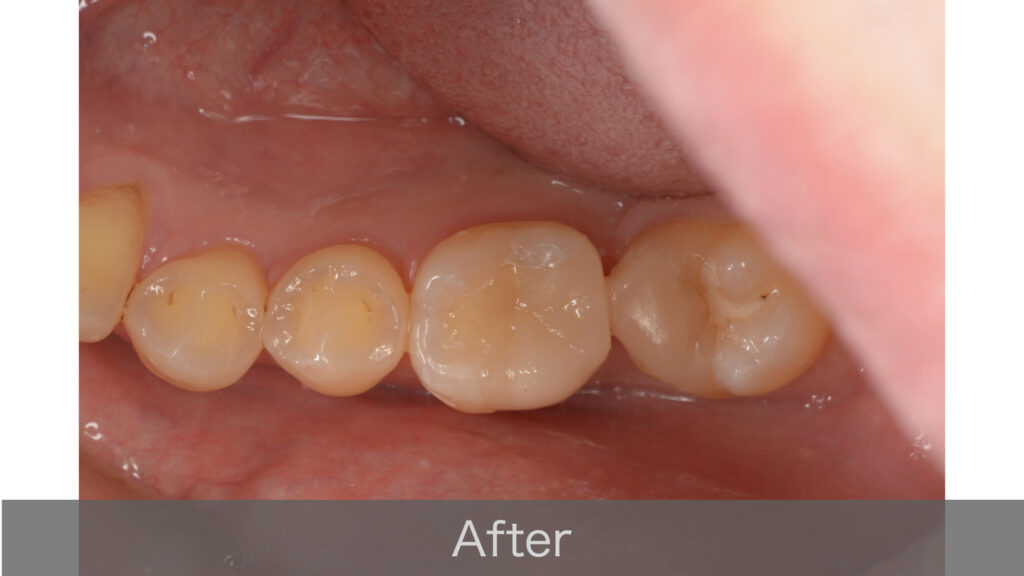

むし歯を除去した部分は、セラミックインレー(白い詰め物)で修復しました。

セラミックは天然の歯に近い色調と透明感があり、見た目が自然です。また、金属の詰め物と比べて歯との適合性が高く、すき間からむし歯が再発するリスクを抑えることができます。

治療は5ヶ月ほどかかりましたが、すべてのステップがスムーズに進みました。